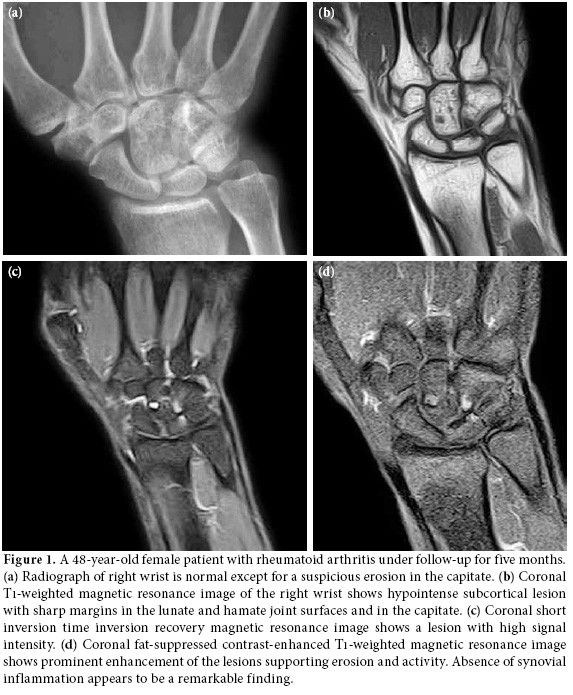

All the cases had a radiograph which was either normal or with suspicious erosions. Magnetic resonance imaging showed 73 (81.1%) bone erosions over different sites in carpal bones, four (4.4%) in distal radius, four (4.4%) in distal ulna, and nine (10%) in proximal metacarpal heads. All the erosions were single or multiple and non-adjacent focal while showing low signal intensity on T1-weighted images with contrast enhancement and high intensity signals on T2-weighted images (Figure 1-3). No bone marrow edema signs which are seen in the advanced stages of the disease as diffuse or converging signal changes were observed. Capitate was the site having the highest number of erosions with 20 (27.3%), followedby triquetral, scaphoid, lunate, trapezoid, hamate, trapezium, and pisiform having 18 (24.6%), 11 (15%), eight (10.9%), six (8.2%), six (8.2%), three (4.1%), and one (1.3%) erosion, respectively.

On MRIs, erosions appear as trabecular bone loss with sharp margins accompanied by cortical defect. Erosions can be more clearly observed following intravenous gadolinium injection.

In the current study, we found bone erosion in all the cases with a normal or suspicious wrist radiograph. Our study shows the superiority of MRI over conventional radiography in detection of early stage erosive changes. By adding contrast studies, detection of erosive changes becomes easier. Moreover, the extent and complications of the disease can be evaluated better.